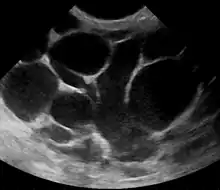

However, if the doctor is not sure whether the mass is an abscess or a tumor, a breast ultrasound may be performed. The ultrasound provides a clear image of the breast tissue and may be helpful in distinguishing between simple mastitis and abscess or in diagnosing an abscess deep in the breast. The test consists of placing an ultrasound probe over the breast.

An abscess (or suspected abscess) in the breast may be treated by ultrasound-guided fine-needle aspiration (percutaneous aspiration) or by surgical incision and drainage; each of these approaches is performed under antibiotic coverage. In case of puerperal breast abscess, breastfeeding from the affected breast should be continued where possible.[25][41]

For small breast abscesses, ultrasound-guided fine needle aspiration such as to completely drain the abscess is widely recognized as a preferred initial management.[42]

One recommended treatment includes antibiotics, ultrasound evaluation and, if fluid is present, ultrasound-guided fine needle aspiration of the abscess with an 18 gauge needle, under saline lavage until clear.[43] The exudate is then sent for microbiological analysis for identification of the pathogen and determination of its antibiotic sensitivity profile,[44] which may in turn give an indication for changing the antibiotics. At follow-up, a mammography is performed if the condition has resolved; otherwise the ultrasound-guided fine-needle aspiration with lavage and microbiological analysis is repeated.[45] If three to five aspirations still do not resolve the condition, percutaneous drainage in combination with placement of an indwelling catheter is indicated, and only if several attempts at ultrasound-guided drainage fail, surgical resection of the inflamed lactiferous ducts (preferably performed after the acute episode is over).[46] It is noted, however, that even the excision of the affected ducts does not necessarily prevent recurrence.[46]